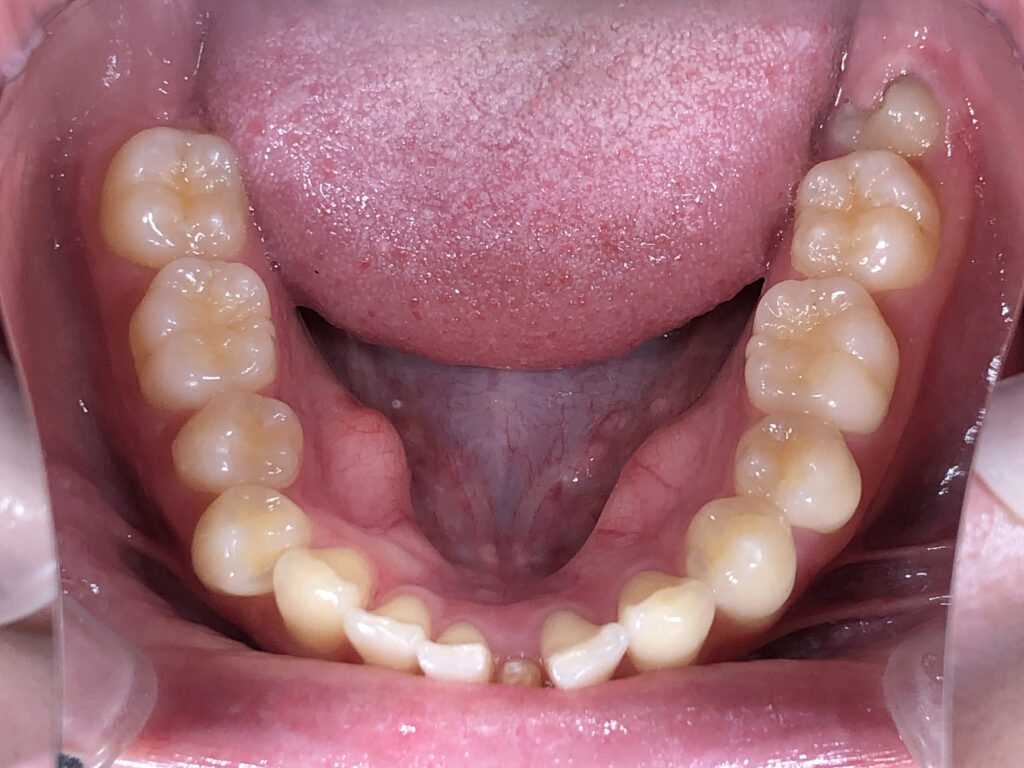

下顎

治療前